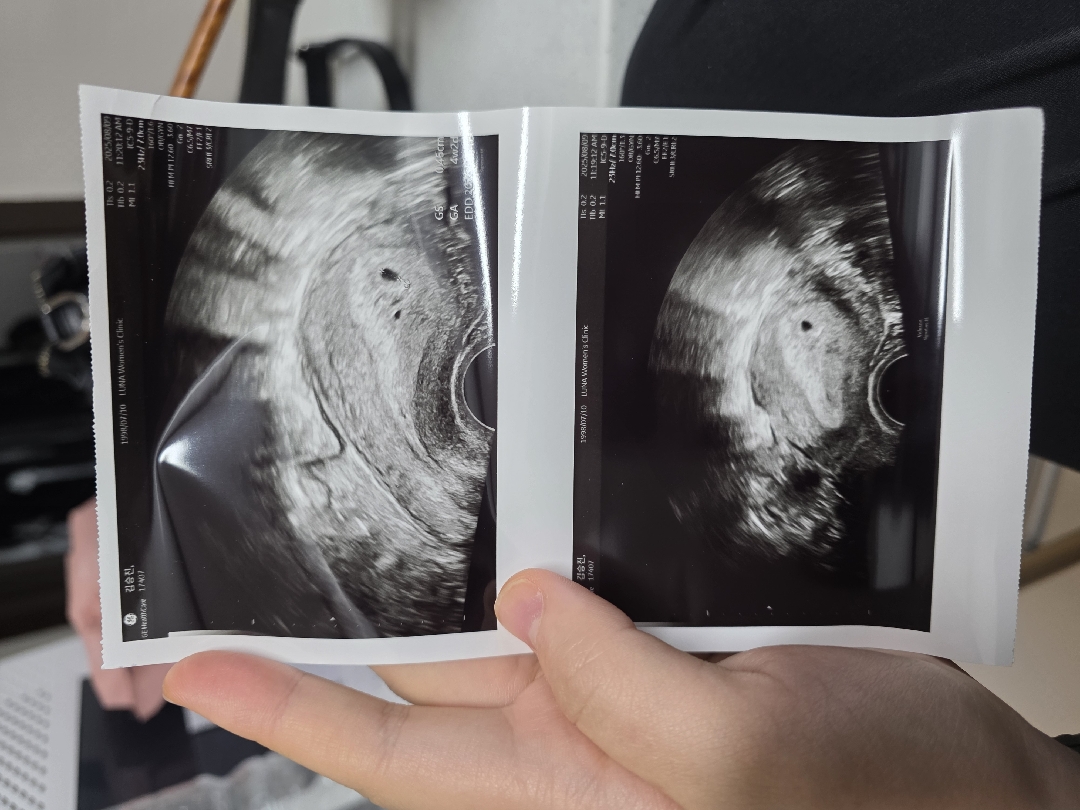

두줄 보고 급한 마음에 저번주 토요일에 애기집이 안보인다고 하여 ㅠㅠㅠ 일주일 뒤인 오늘 애기집 보고 왔습니당..!! 평균 38일 정도로 주수로 확인했을 때는 6주 2일인데.. 초음파 상으로는 4주 2일이라네용 이제 막 지어진 집이랍니당 ㅎㅎㅎ

맞아요!! 다음주에는 보일 것 같다고 하더라구요 ! ㅎㅎㅎㅎㅎ (기대중)